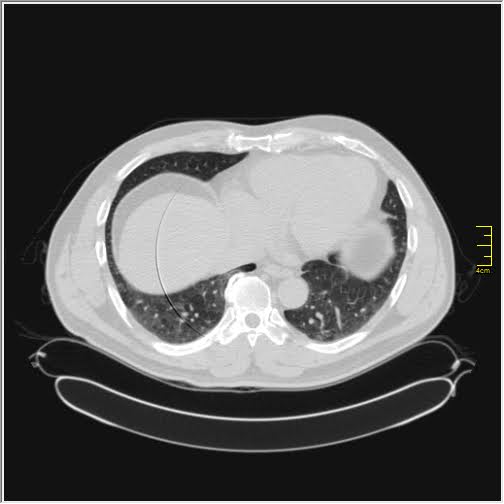

Foto: Aleksandar Ivković Foto: Aleksandar Ivković Foto: Aleksandar Ivković Zastrašujući snimci skenera pluća od 1. do 15. dana kovida autor: Božica Luković Zdravlje 26. nov. 2020. 12:33 > 26. nov. 2020. 13:35 0 Podeli vest: Kovid 19 je nepredvidiva bolest koja u razmaku od par dana može iz blage da preraste u opasnu po život. Kako koronvirus utiče na pluća iz dana u dan, pokazao je na snimcima CT skenera srpski radiolog Aleksandar Ivković. Podeli vest: Oglas Lekar iz Niša na svom blogu "Ljudi i ostale laži" redovno piše o svim važnim temama u vezi sa koronavirusom, a sada je odlučio da prikaže CT skenere pluća osobe obolele od kovida 19.Objasio je šta lekari tačno prate kada su u pitanju snimci pluća, ali i kako se te stavke menjaju kako bolest napreduje.Njegovu objavu prenosimo u celosti."Vraćam se na svoju usku struku (da ne bude da se mešam u tuđu). Kompjuterizovana tomografija, skener ili CT je metoda pregleda koja je superiorna kod zapaljenskih bolesti pluća. Kod kovida 19 se pokazala kao nezamenjiva u diferencijaciji u odnosu na ostale bolesti. Tačnost nalaza na plućima je visoka. Šta mi to možemo videti i kako tumačimo? Stvari koje pratimo su:- Ground glass konsolidacije (GGO).To su one bele "mrlje" na snimcima koje su karakteristične za ovu bolest. Nazivaju se "ground glass" svuda. Izgledaju kao da se taj deo pluća gleda kroz mlečno staklo, kao neka vrsta mikromozaika. Foto: Aleksandar Ivković | Foto: Aleksandar Ivković - Crazy paving.To su linearna zadebljanja koja se nekada vide u ground glass konsolidacijama. Ona nastaju kasnije, ne javljaju se pre GGO. Neko ih opisuje kao da pijani majstori slažu pločice. Na slikama se to vidi kao nepravilna zadebljanja unutar GGO, složena bez ikakvog reda. Foto: Aleksandar Ivković | Foto: Aleksandar Ivković - Vaskularne dilatacije. Dolazi do zapaljenskog procesa krvnih sudova i/ili do zastoja tako da su nam na snimcima krvni sudovi "deblji". Foto: Aleksandar Ivković | Foto: Aleksandar Ivković - Trakcione bronhiektazije. To su proširenja vazdušnog prostora (ali ne onog koji učestvuje u disanju) koja nastaju kada stradaju alveole i proširuje se prostor između njih. Foto: Aleksandar Ivković | Foto: Aleksandar Ivković - Arhitektonske distorzije. Pojava traka blizu pleure koje nastaju propadanja plućnog tkiva i nastanka fibroznog. Foto: Aleksandar Ivković | Foto: Aleksandar Ivković Svaki od ovih znaka se može javiti i kod drugih bolesti ali svi zajedno su specifični za kovid-19Da bi objasnili stanje koristimo Severity Score. On služi za procenu ozbiljnosti bolesti. Pluća se sastoje od pet lobusa. Procenjuje se svaki pojedinačno ocenama od 0 do 5. To znači da se skor kreće od 0 do 25.0 - znači da nema GGO konsolidacija1- znači da je manje od 5% tog lobusa zahvaćeno2 - znači da je zahvaćeno od 5 do 25% tog lobusa3 - znači da je zahvaćeno 26 do 50% tog lobusa4 - znači da je zahvaćeno 51 do 75% tog lobusa5 - znači da je zahvaćeno više od 75% tog lobusa Na CT razlikujemo 4 faze (najčešće ali nije decidirano tako) Rana faza (0 do 4. dan) - pojedinačne GGO, neka crazy paving, nizak skor Foto: Aleksandar Ivković | Foto: Aleksandar Ivković Progresivna faza (5. do 8. dan) - povećanje broja GGO i crazy paving Foto: Aleksandar Ivković | Foto: Aleksandar Ivković Pik faza (10. do 13. dan) - javljaju se konsolidacije pluća, to znači da veliki delovi pluća izgledaju kao velike bele površine a označavaju delove pluća koji su masa koja koja je u celini zahvaćena zapaljenskim procesom. Foto: Aleksandar Ivković | Foto: Aleksandar Ivković Faza rezolucije (posle 14. dana) - vraćanje delova pluća u normalu ili smrt Foto: Aleksandar Ivković | Foto: Aleksandar Ivković Iskustveno smo došli do skora 15 koji predstavlja neku granicu između verovatno dobrog i verovatno lošeg ishoda. Samo tumačenje zavisi od faze bolesti. Naš nalaz je samo deo procene i ne menja laboratorijske i pulmološke, kao ni ostale. Svaki nalaz zajedno daje ukupnu sliku bolesti. Foto: Aleksandar Ivković | Foto: Aleksandar Ivković Nalaz je u88% slučajeva sa obe strane,88% ground glass,80% posteriorno,79% multilobularno,76% periferno i30% konsolidacijeTo je posao radiologa, to je moj posao. Sasvim sigurno je da bez ovih slika lečenje ne bi bilo lako. Pacijente delimo na lake - one koji nemaju tegobe, teške - one koji imaju zahvaćeno do 50% pluća i kritične a to su oni kod kojih je više od 50% zahvaćeno", piše dr Ivković.***Bonus video:https://www.youtube.com/watch?v=fYeYlhqeD5cPratite nas i na društvenim mrežama:FacebookTwitterInstagram Revolucija iz Niša: Test na koronu koji predviđa tok bolesti Zdravlje 0 Tekst naučnika koji ruši sve zavere o koroni - i daje nadu Zdravlje 0 72 sata pakla od kad su me zabolela pluća u kovid Srbiji Zdravlje 0 aleksandar ivković ct skener koronavirus kovid-19 pluća Pratite nas na društvenim mrežama: Koje je tvoje mišljenje o ovoj temi? Učestvuj u diskusiji ili pročitaj komentare Budite prvi koji će ostaviti komentar Pošalji komentar Pročitaj komentare (0)